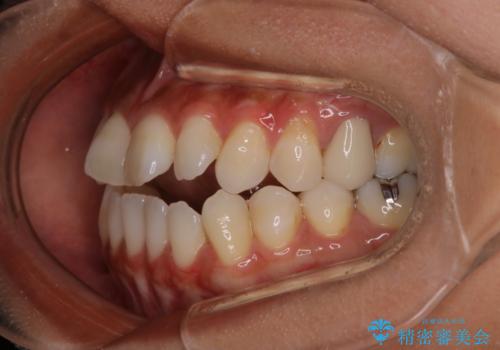

- 開咬を主訴に来院されました。前歯部に開咬、右側大臼歯部にクロスバイトが認められます。ワイヤー矯正の審美装置で治療し、ゴム掛けを行いながら噛み合わせを改善しました。

主訴である開咬と右側大臼歯部クロスバイトを改善でき、しっかりと噛むことができるようになりました。